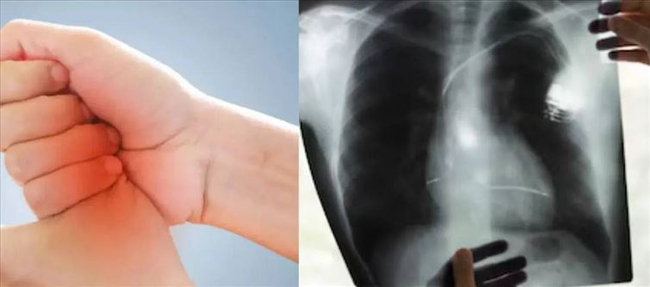

Clubbing with the fingers

The initial symptom is finger clubbing, a condition that often affects both hands and fingers and appears to progress gradually. The surrounding skin may appear red at this time, and the nail's base may first grow softer. The nail may bend more than usual if the cone that forms between the nail bed and the skin folds directly under the cuticle grows. Clubbing between the fingers often takes years to develop, but in certain situations, such as lung abscess, it may occur more quickly, according to cancer Research UK.

Swelling in the fingers and wrists

In addition to joint discomfort and swelling, some patients with lung cancer may also have edema in their fingers and nails. Hypertrophic pulmonary osteoarthropathy is the name given to this illness. Finger and wrist swelling, as well as fingers sticking together, are signs of HPOA. According to cancer Research UK, some patients with lung cancer develop hypertrophic pulmonary osteoarthropathy.